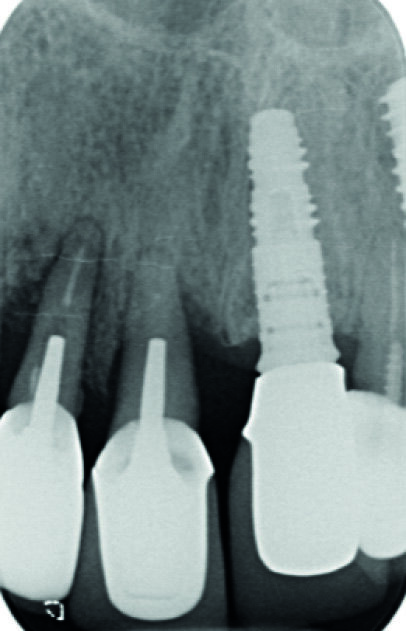

Fig. 7 : Radiographie « long-cône » postopératoire. Notez l’image résiduelle de l’alvéole au niveau de l’implant en 12.

Les implants sont vissés à la main à l’aide d’une clé dynamométrique. Nous vissons ensuite les piliers temporaires (Avinent), et les couronnes provisoires en résine PMMA sont rebasées et scellées (laboratoire Crown Ceram) avant de suturer le lambeau. À ce stade, notons que le second avantage du lambeau est de pouvoir aussi contrôler parfaitement l’adaptation prothétique, et d’éviter toute fusée de ciment de scellement. Une radio de contrôle postopératoire est réalisée (Fig. 7).

La patiente est revue à huit jours. Les suites opératoires se sont bien passées et la prise d’antalgique très limitée. Les sutures sont retirées. Puis la patiente est revue en contrôle à deux mois (Fig. 8), trois mois (Fig. 9) et quatre mois. Les radiographies de contrôles montrent un gain osseux au niveau de l’implant en 12 et une parfaite intégration des deux implants. Les cicatrisations clinique et osseuse sont très bonnes et il est décidé de passer à la prothèse définitive. Les couronnes et piliers provisoires sont retirés et les tissus mous vérifiés (Fig. 10).